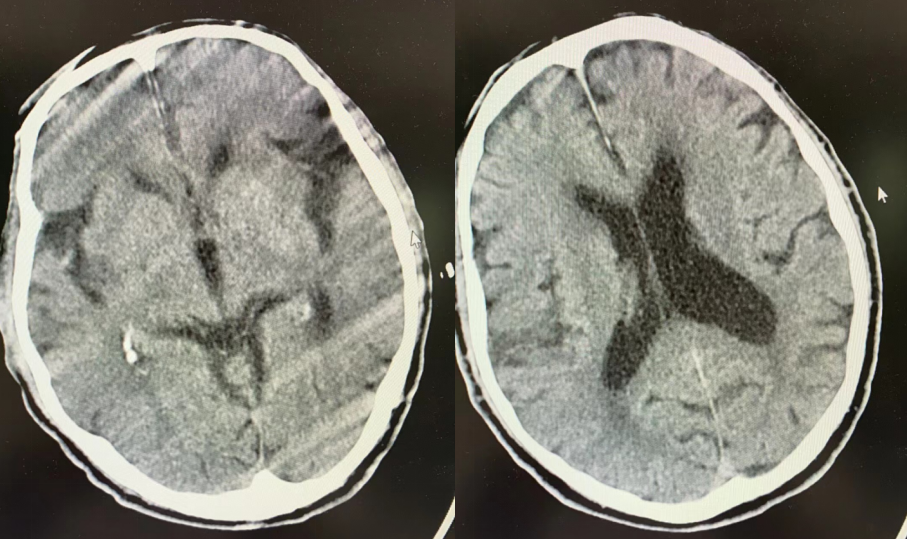

图三:次日CT片

术后次日复查CT,无颅内出血及造影剂滞留。TCD及颈动脉彩超提示右侧颈内动脉系统血供良好。